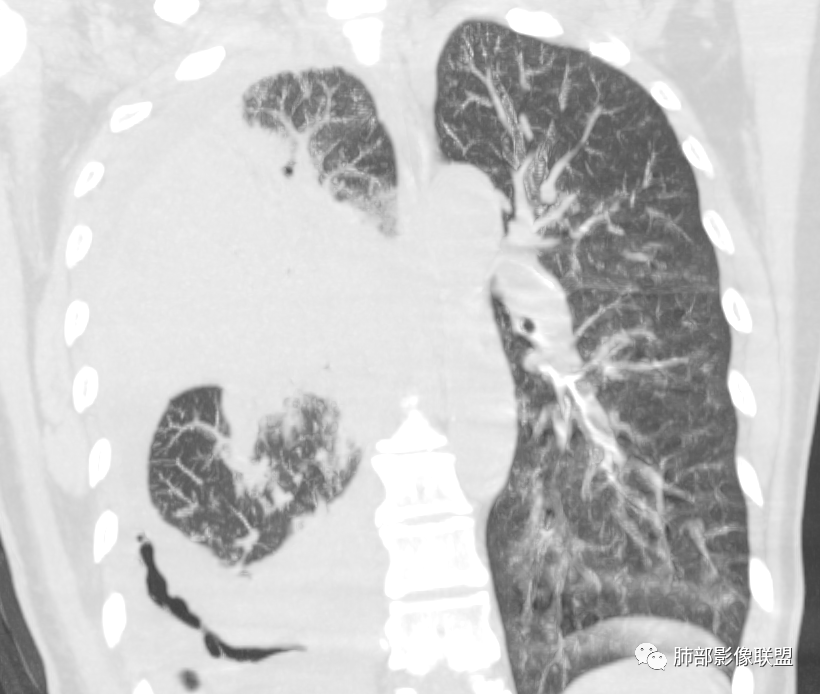

中老年女性,急性病史,全身症状,提示全身多部位受累。5,29:右肺大量胸水压迫,导致肺叶不张夹杂其中,无法观察病灶实质;左肺病灶沿支气管血管束走向,无叶段性分布,提示间质为主病变。

10天后:胸水减少,右肺病变较前增大,内部未见坏死,含气支气管通畅。

下叶病变明显沿血管束分布

大叶性肺炎、无坏死空洞、间质为主,沿支气管血管束分布,伴随胸水。

常规鉴别:鹦鹉热、肺链、军团、腺病毒、结核。肺链、军团——肺泡性为主,应该外围胸膜下起源,不支持。

整体病灶边缘膨隆,周围网格+GGO

肺门区支气管受压、狭窄

从现在的图像看:胸水压迫、推移。

病灶本身占位效应,边缘膨隆,边缘没有收缩的迹象,也就是说支气管周围没有牵拉的因素导致其扩张,我们只能考虑支气管本身导致的扩张。

从支气管的改变:要警惕淋巴瘤。左肺病变沿支气管血管束分布,支持间质为主病变。